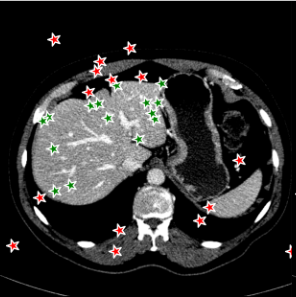

Points are the most fundamental interactions in semi-automatic annotation tools, but also most unpredictable. To train a new point-based prompt tailored to a specific annotation task, a stochastic process is employed wherein points are randomly sampled from the interval of within both the background and foreground regions of each annotated slice during every iteration of the training process. In this work, three distinct point selection schemes has also been investigated, namely ‘uniform’, ‘center’ and ‘boundary’. An example is illustrated in Fig. 5. In the case of uniform sampling, points are random selected with uniform distribution within the mask region. For center sampling, we primarily selected the points at the central location within the target region, by applying a distance transform. Conversely, the boundary sampling mainly selects the point near the boundary.

For 3D dataset, the SAM model will be initially trained on several randomly selected annotated slices, and then tested on the remaining slices. For 2D dataset, such as Kidney-US and Nuclear-Hist, the SAM model will be initially trained on several randomly selected cases, and test on other cases. We randomly sampled points from both foreground and background regions to train the new prompt. Each case will be trained and tested, individually. Figure 7 demonstrated the performance of the point-based SAM model. As the figure shows, single point on the target has shown remarkable segmentation performances using SAM even with only 2 annotated slices for the prompt training, compared to the original SAM model. Segmentation results of Kidney-CT are visualized in Figure 8. Segmentation results of one test slice is shown to demonstrate the significant improvement of SAM . Comparison results with other state-of-the-art segmentation results are shown in Table 2 including both fully-supervised (such as nnUNet, UNetr), fine-tune based SAM segmentation method (such as MedSAM, MSA).

The segmentation results of different point selection schemes for the Kidney-CT dataset is demonstrated in Figure 9. Uniform random selection scheme shows slightly better variation compared to other scheme but there is no significant differences between each scheme entirely.